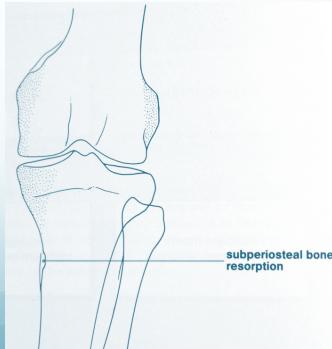

- Sub-periosteal bone resorption (most specific finding)

- Sub-periosteal resorption: middle phalanges, tibial shaft

Sub-periosteal bone resorption

- Most useful sign

- Virtually Diagnostic

- Location

Subperiosteal bone resorption (straight arrow), resorption of the tip of the terminal phalanx and the altered bone architecture. Arterial calcification is also present (curved arrow).